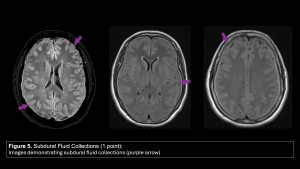

- Subdural Fluid Collections (1 point):

- Positive: Presence of bilateral subdural hygromas (fluid signal similar to CSF).